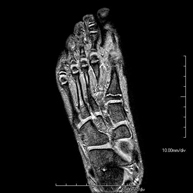

Exploració per a l'estudi de lesions a tendons, lligaments i petites articulacions. És la prova que permet diagnosticar millor les capsulitis freqüents per traumatisme, l'artrosi i els trencaments de tendons. La durada aproximada és de 20 minuts. No utilitza radiació ionitzant. - RM de Malucs

Exploració per a l'estudi de lesions en tendons, músculs i petites articulacions. Permet valorar amb eficàcia les lesions al cartílag. També és de molta utilitat per completar l'exploració ecogràfica prèvia. No empra radiació ionitzant. Té una durada aproximada de 20 minuts. - Artro-RM d'Espatlla